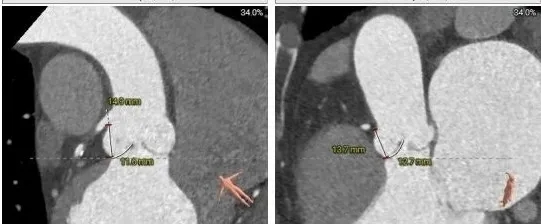

主动脉根部测量

周长径28.8

周长径29.5

L:48.2 N:47.3 R:24.8

周长径45.4

周长径45.5

L:28.1 N:27.3 R:24.5

三叶式主动脉瓣

流出道敞口

瓦氏窦、升主扩张

瓣叶轻微增厚

瓣上结构测量

周长径28.6

周长径29.9

周长径31.5

周长径33.8

周长径35.4

周长径35.8

瓣上空间逐渐增大,瓣上瓣叶轻微增厚,0-6mm可提供锚定力

外周入路评估

外周血管无明显病

66°横位心

瓣膜型号:ScienCrown TAVTF32mm(oversize11.1%)

入路选择:经心尖入路(患者横位心,根部明显扩张故选择心尖入路)

手术操作:该患者流出道敞口型,流出道无锚定力,瓣上空间扩张,需充分利用瓣环锚定;同时瓣膜横位心验证,术中需充分利用瓣膜全可回收功能,评估瓣膜稳定性